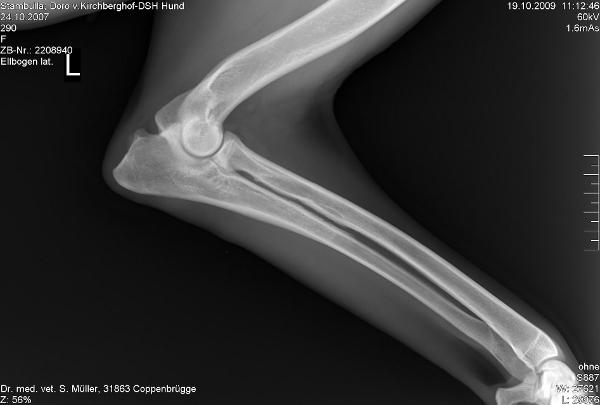

HD/ED:

a-fast-normal              a-noch zugelassen